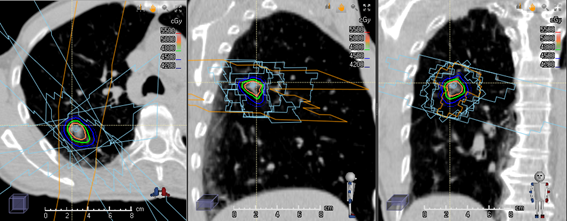

治療計画装置

治療計画CTで撮影した画像をもとに、標的と正常組織を定義し、標的に対してビームの入射方向や照射野及び投与線量を規定し、線量分布を取得します。その後、線量体積ヒストグラム(DVH:dose volume histogram)により、標的への線量均一性や正常組織への線量がどの程度付与されるか評価します。